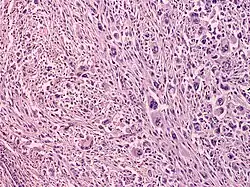

Atypical fibroxanthoma (AFX) is frequently found to have a well-circumscribed, nonencapsulated dermal tumor that is either contiguous with the epidermis or separated from it by a narrow zone of collagen (Grenz zone); plump spindle cells with prominent nuclei, epithelioid cells, and multinucleated giant cells; atypical mitoses and severe cellular pleomorphism; and varying presence of thin or ulcerated epidermis or peripheral epidermal collarette.[9]